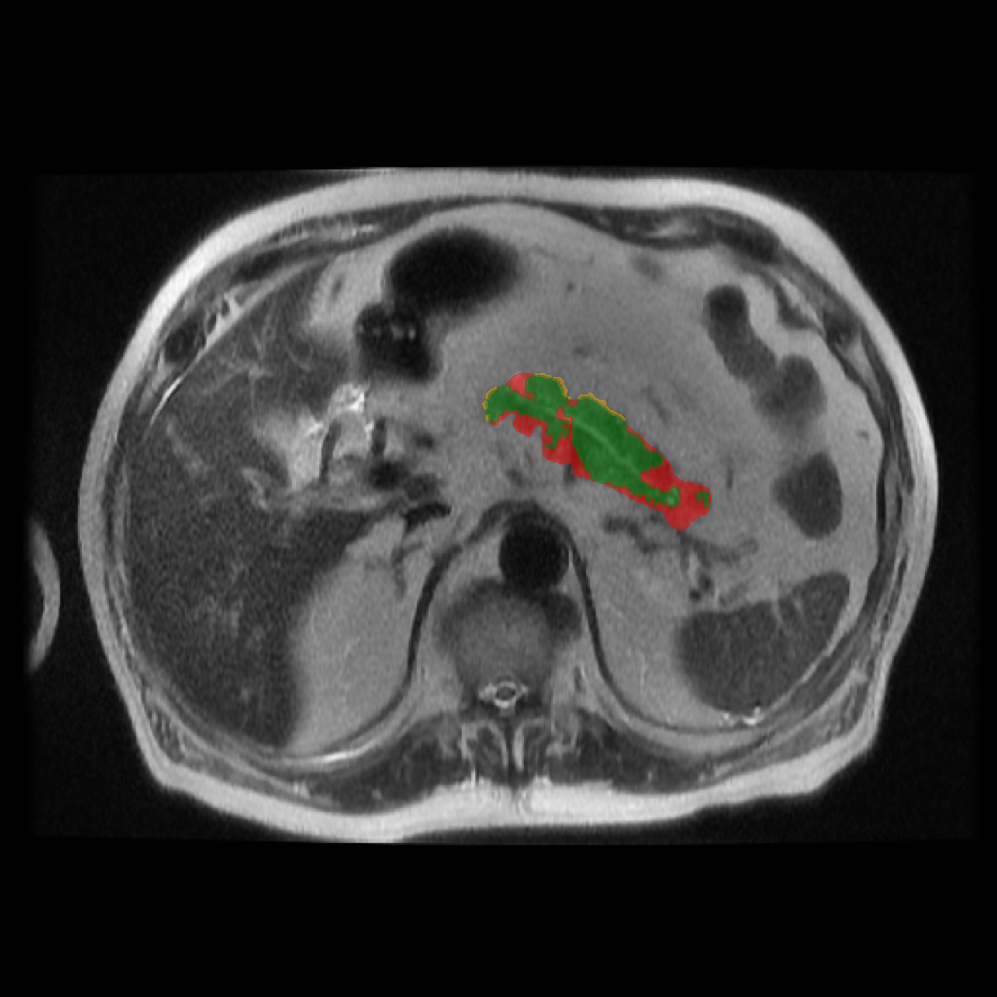

Accurate pancreas segmentation is a critical prerequisite for precise cyst analysis and classification. Recently, we developed PanSegNet [zhang2025large], a novel segmentation architecture incorporating linear self-attention layers [zhang2022dynamic] within the nnUNet framework [isensee2021nnu] to enhance global information modeling capabilities while maintaining computational efficiency (Fig. 1). PanSegNet demonstrated exceptional segmentation performance across both T1W and T2W modalities, achieving mean dice scores of 86.817.30% and 89.626.38%, respectively (Table 1, Fig. 2b-c). This performance significantly exceeded that of Swin-UNETR [hatamizadeh2021swin], one of the most used state-of-the-art transformer-based medical segmentation models, which achieved dice scores of 79.091.40% and 76.290.66% for T1W and T2W, respectively (). In this study, we integrated PanSegNet into our Cyst-X engine along with a classifier for risk prediction. In Section 2.2, we show that the choice of segmentation model affects the classification results. The performance advantage of PanSegNet was consistent across all seven medical centers, demonstrating robust generalization despite variations in imaging protocols and equipment (Table 1). This cross-institutional reliability is particularly important for clinical applications, where model performance must remain consistent regardless of imaging site or acquisition parameters.

Each patient was categorized into one of these three ground truth classes: no risk/control, IPMN low-risk, or IPMN high-risk. To evaluate variability in image acquisition, we applied uniform manifold approximation and projection (UMAP) to image quality indicators, revealing distinct clustering patterns by imaging center and slice thickness. This heterogeneity reflects real-world clinical variability, enhancing the dataset’s generalizability while presenting technical challenges for model development. Fig. 6 shows examples of low-grade, high-grade, and cancer developing IPMNs from the Cyst-X dataset.